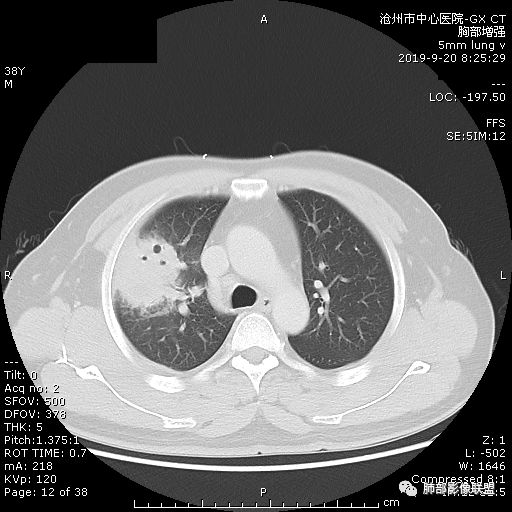

膨隆、深分叶,支气管截断,叶裂推移,淋巴结肿大,均提示恶性可能;但毕竟年轻,血象高,内部坏死边界清晰,局部收缩感,提示感染可能,另外内部数个小空洞改变,是扩张支气管吗?需要连续层面看,如果是,就更支持感染。

首先病灶示:跨尖、后、前三段,局部突入中叶;大家理解一下:是不是光滑的地方有叶裂,毛糙的地方没叶裂。

周围GGO,不是远端;

而且这个病灶明显跨段,属于外围的病变,不受某一段支气管的局限;

宽基底,胸膜增厚

3.ct表现:肺脓肿可呈结节状或团块状,有时呈不规则形,气道来源肺脓肿常单发,血行来源常多发,边缘模糊,部分病灶周围可见片状肺实变及磨玻璃影;病灶中央为液化坏死区,若脓肿与支气管相通,脓液排出可形成空洞,空洞内可形成液平;急性肺脓肿内壁多不规则;慢性肺脓肿洞壁较厚,一般不规则或形成多房空洞:CT增强扫描空洞壁可见强化,空洞壁为纤维肉芽组织,呈典型的环形强化;慢性肺脓肿周围可有较广泛的纤维索条影,可伴支气管扩张.肺